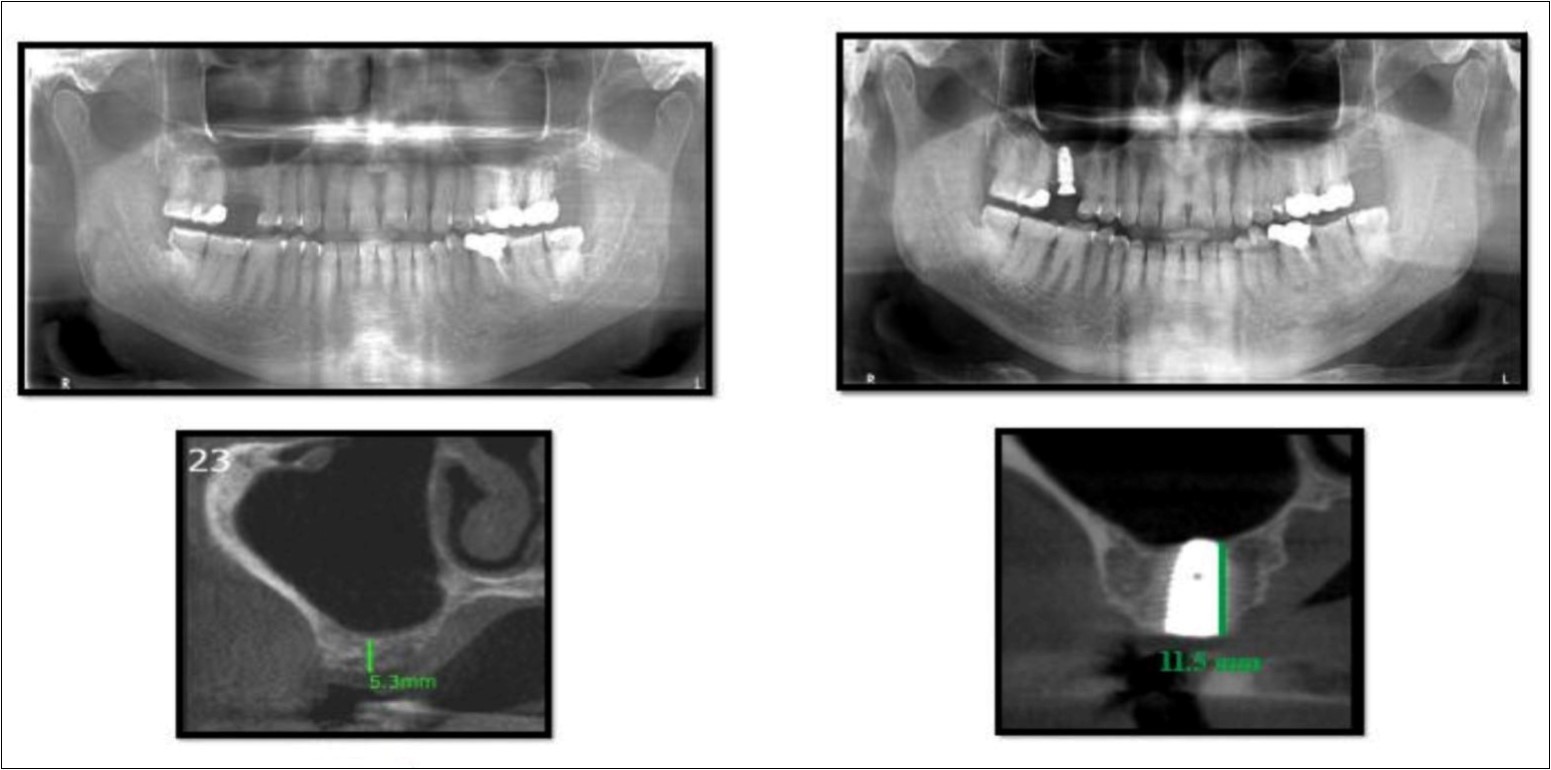

With a pre-operative residual bone height of 0.8 mm in 16 region and 1.5 mm in 17 region, direct sinus augmentation was carried-out in a 40 year old male patient followed by implant placement of 3.75 x 11.5 dimensions as a single step procedure. Lateral window was created and synthetic graft material was dispensed through the lateral osteotomy site to maintain the elevated sinus membrane followed by placement of two dental implants through the crestal approach measuring 3.75 x 11.5 mm under local anesthesia and strict aseptic protocols. At the end of 6 months, a CBCT scan was advised to evaluate the increase in bone height which was 11 mm and 10.8 mm in 16 and 17 region respectively. (Figure 1, Figure 2)

Figure 1.Pre-operative Orthopantomograph and cross sections of CBCT showing residual alveolar bone height

Figure 2.Post-operative Orthopantomograph and cross sections of CBCT showing an increase in residual alveolar bone height